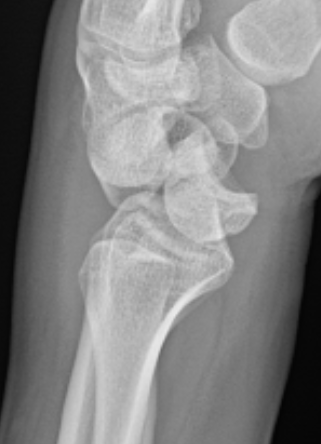

Lateral xray

Distal radius / lunate / capitate: not aligned, spilled teacup

Normal versus spilled tea cup appearance on lateral with spilled tea cup